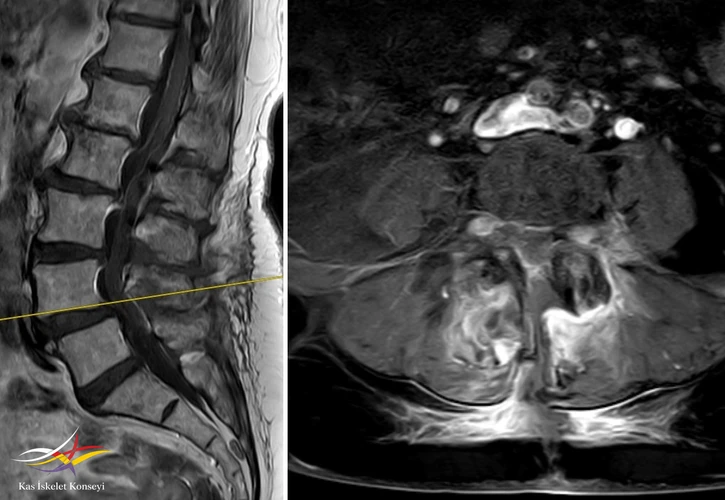

Resim 5. L4-5 seviyesinde dejeneratif listezis ve belirgin kanal darlığı görülmekte.

Resim 6. Sagitaal MRG ve MRG myelografide darlık seviyeleri.